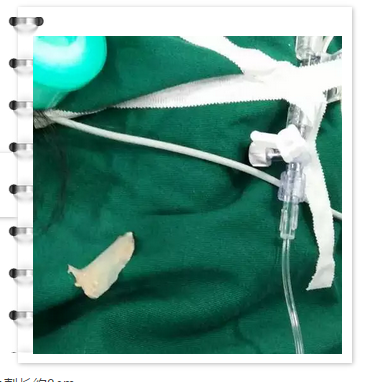

Ms. Liu, deputy chief physician of the department of digestive endoscopy, performed endoscopic removal of esophageal foreign body for the patient at about 8:00 PM on March 20. The transparent cap was placed at the end of the lens, it entered the esophagus smoothly. The foreign body was incarcerated into the left side wall, 25cm from the incisor, with one end penetrating into the wall of the esophagus. Director Liu used foreign body forceps to clamp the end of the foreign body and got it into the esophageal cavity. Then, the foreign body was rotated with the endoscope and pulled out of the esophagus. Further microscopic observation showed a little mucosal damage on the left side of the esophagus without obvious bleeding. The foreign body was about 3cm long. The patient underwent conservative treatment including fasting, anti-inflammatory and hemostasis treatment, and left hospital on March 21st.

![]() ![]() • the 3cm long spine from patient’s esophagus Tips: Esophageal foreign body incarceration is common. It is often caused by the patient's passive (improper eating) or active reasons (intentional swallowing of mental illness patients and criminal suspects, etc.). For foreign bodies caused by improper eating, many people believe that they can be swallowed by drinking vinegar or swallowing rice balls. However, important organs and tissues are dispersed around the esophagus, such as trachea, large blood vessels, heart, connective tissue, nerve, mediastinum, etc. If a foreign body is forcibly swallowed, it will cause fatal risks such as esophageal perforation, mediastinal infection, large blood vessel bleeding, puncture into the heart, etc. In children, high esophagotracheal fistula can be caused. For the treatment of esophageal foreign body, there are three main methods: conservative treatment, endoscopic treatment and surgical treatment. Conservative treatment is generally applicable to small blunt foreign bodies below the duodenum. If conservative treatment fails, surgical treatment is required. Compared with traditional thoracotomy for esophageal foreign body removal, endoscopic esophageal foreign body removal has the advantages of less trauma, no thoracotomy, rapid recovery, low cost and fewer complications, and has the dual value of diagnosis and treatment. Most of the esophageal foreign bodies can be removed by endoscopy, but for the foreign bodies without infection in the great vessels that can be removed by endoscopy, CT re-examination should be conducted after foreign bodies discharge to prevent the occurrence of traumatic pseudoaneurysm. The foreign body of large blood vessels that cannot be removed by endoscope alone still needs endoscopic combined surgery, so as to avoid the complications of postoperative fistula and stenosis. In the case of patients with infection or even abscess caused by foreign body puncture into the great vessels, endoscopic intervention combined with total covered great vessels stenting is required for treatment. In this case, the shortest distance between the esophageal foreign body and the aortic arch was only about 2.4mm, but the perforation of the esophagus had not yet been caused. The endoscopic removal was made through the full evaluation and the accurate endoscopic technique, so as to avoid the open-chest surgery. Chest CTA showed the foreign body is about 2.4mm from the aortic arch. The patient was firstly admitted in the department of thoracic surgery. After the consultation of digestive endoscopy division, the physicians concluded that the esophageal foreign body could be retrieved through gastroscope. Prof. Fan Zhining, director of the endoscopic department proposed the operation with the cooperation of doctors for thoracic surgery. As the foreign body was close to the aortic arch, it is a risky case. If there were any urgent situation during operation, thoracic surgery should be carried out immediately. Ms. Liu, deputy chief physician of the department of digestive endoscopy, performed endoscopic removal of esophageal foreign body for the patient at about 8:00 PM on March 20. The transparent cap was placed at the end of the lens, it entered the esophagus smoothly. The foreign body was incarcerated into the left side wall, 25cm from the incisor, with one end penetrating into the wall of the esophagus. Director Liu used foreign body forceps to clamp the end of the foreign body and got it into the esophageal cavity. Then, the foreign body was rotated with the endoscope and pulled out of the esophagus. Further microscopic observation showed a little mucosal damage on the left side of the esophagus without obvious bleeding. The foreign body was about 3cm long. The patient underwent conservative treatment including fasting, anti-inflammatory and hemostasis treatment, and left hospital on March 21st.